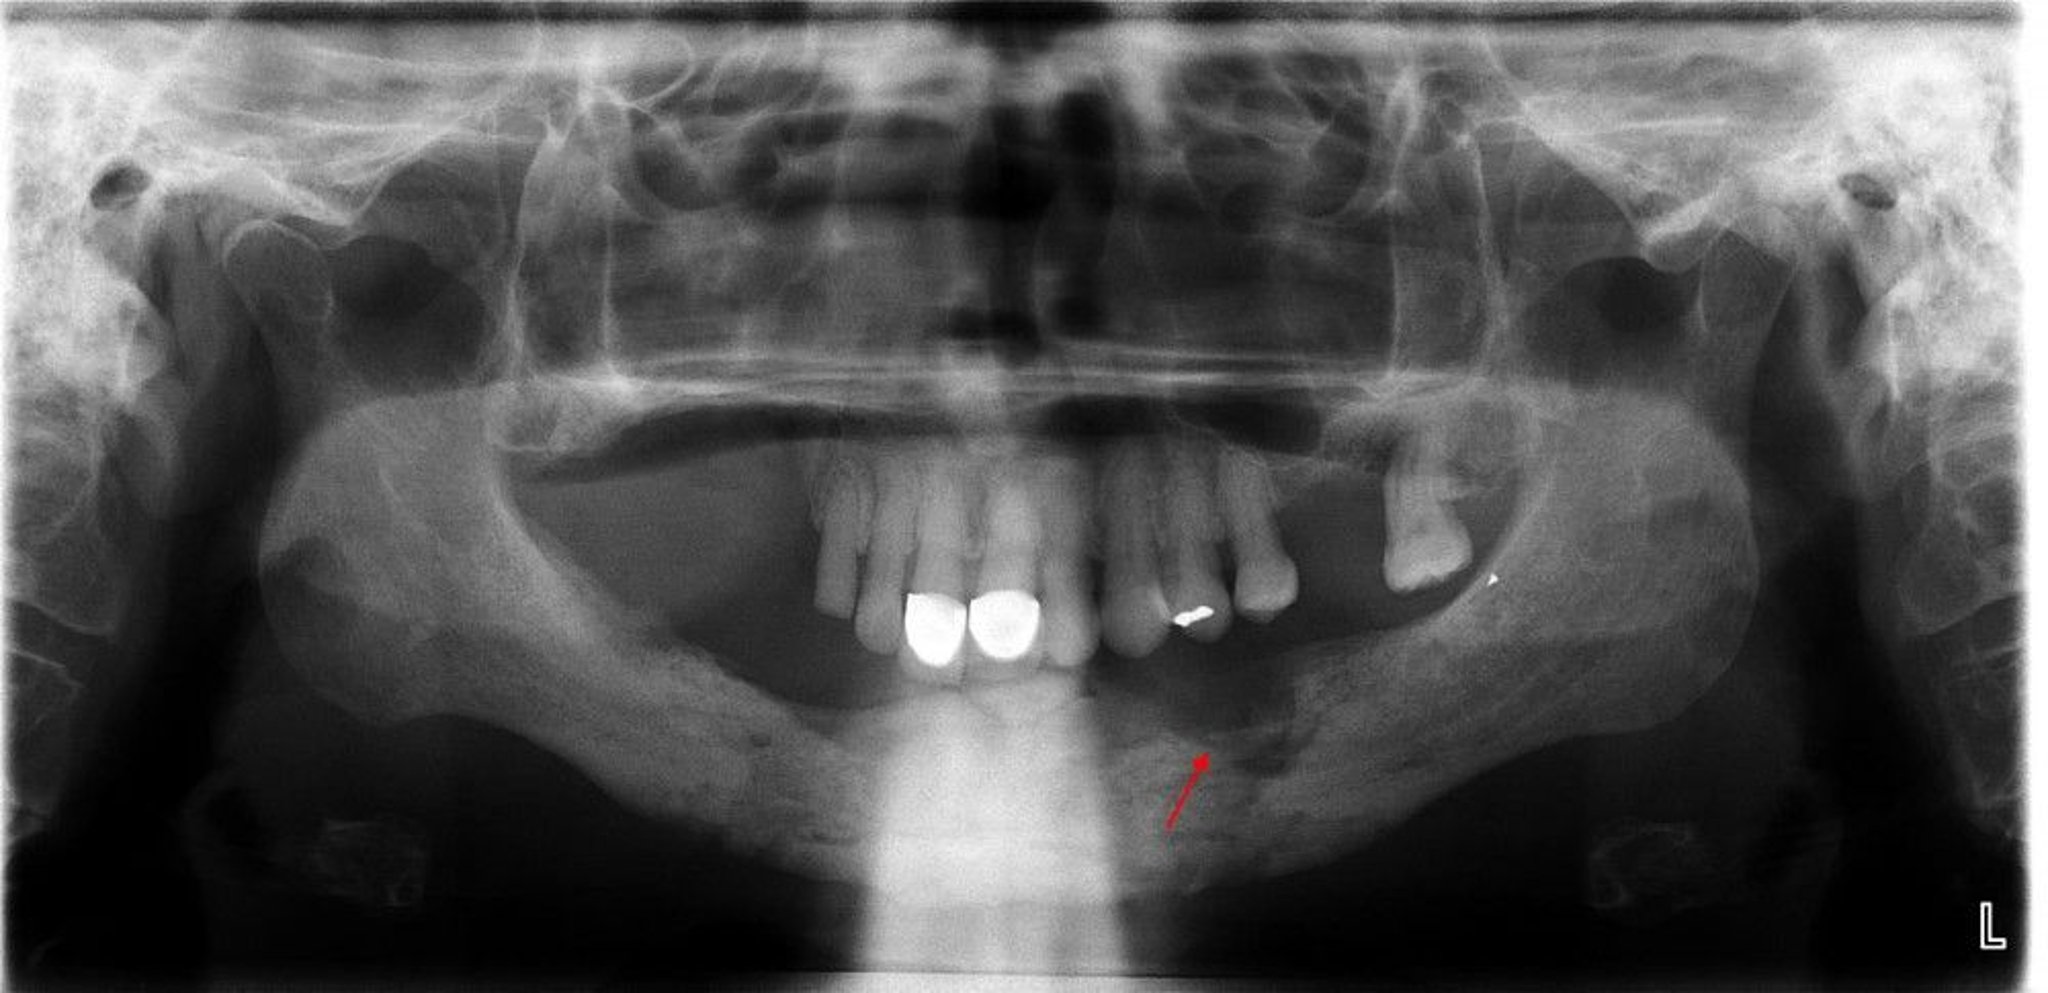

Osteomyelitis

This radiograph reveals osteomyelitis with an evident sequestrum (nonviable bone) noted in the left mandibular quadrant (arrow).

Image courtesy of Byron (Pete) Benson, DDS, MS, Texas A&M University Baylor College of Dentistry.